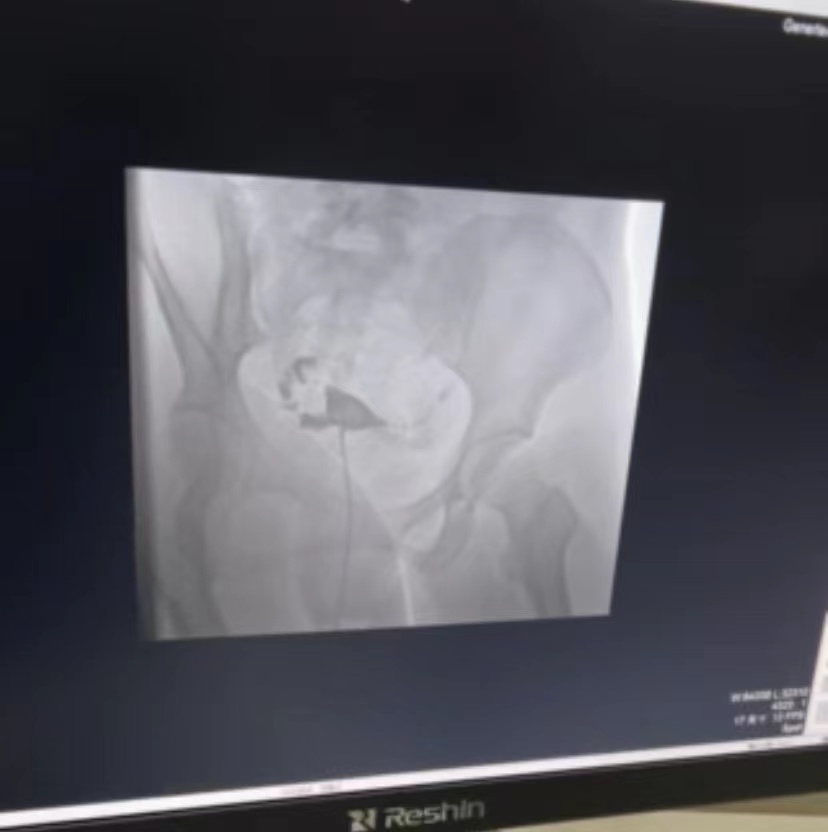

近年来不孕症的发病率逐年攀升,严重困扰有生育需求的妇女,我院妇科开设了不孕不育门诊,而子宫输卵管X线造影检查则是重要的检查手段之一,为此妇科联合医学影像科开展了子宫输卵管X线造影。

子宫输卵管X线造影检查是以一种油溶性或水溶性造影剂,在一定压力下注入于子宫与输卵管使之显影,这样不但能提示输卵管是否通畅,显示堵塞的部位,还能观察子宫腔形态等。其适应症包括:

5.子宫颈管形态异常等。术中如果发现输卵管通而不畅或梗阻、积水,则进行输卵管再通治疗可大大提高受孕几率。

现妇科联合医学影像科已全面开展了子宫输卵管X线造影,希望此项检查能为患者提供更全面、更优质的医疗服务,为不孕症女性的求子之路点亮明灯。